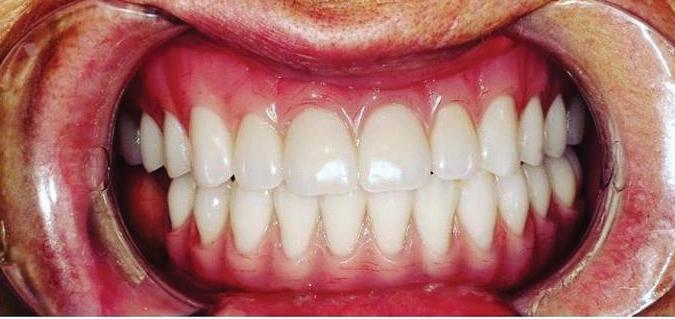

Submitted By Sivakumar Sreenivasan, DMD, MDS

Can just four implants replace all of the teeth on the top or the bottom of your mouth? Thanks to advances in dental implant technology, that answer is a resounding yes.

Believe it or not, tooth loss is extremely common among adults, especially as we age. In fact, more than 35 million people in America are missing all of their upper and/or lower teeth. Rather than living with the discomfort and hassles of dentures, many people are opting for what is called “all-onfour” dental implant restoration.

All-On-Four: One Full Arch Of Teeth, Four Dental Implants

A Reason To Smile Again

able technique for replacing teeth, you should first understand what a dental implant is. An implant is a small titanium screw that fits inside your jawbone and replaces the root-part of a missing tooth. Minor surgery is required to insert the implants. Once the implant is in place, a crown is attached to give you a highly realistic-looking and functional prosthetic tooth.

Here’s where it gets really interesting: You do not need a dental implant for each and every one of your missing teeth. All you need is four precisely placed implants on the top of your mouth, and four on the bottom, to restore your full smile. That’s the beauty of the all-on-four. And because the implant is made of titanium, it has the unique ability to fuse to living bone and function as part of it. So eventually, the dental implant becomes part of the jawbone and serves as a strong, long-lasting foundation for your new teeth.

Besides ensuring that your implants are permanently fixed in place,

Thanks to advances in dental implant technology, just four implants can replace all of the teeth on the top or the bottom of your mouth.

this bone fusion has another important benefit: it prevents future bone loss in the jaw. This helps to maintain a more youthful facial structure – and better oral health. But perhaps the biggest surprise about the all-on-four is how quickly it can transform your life.

What’s The All-On-Four Dental Implant Procedure Like?

It can be scary to get implants for the first time. Most of that fear is probably due to the uncertainty, so here is the step-by-step process for getting an All-On-Four dental implant.

First, your dentist will want to make sure your comfortable, so either local or general anesthesia will be administered.

Second, the dentist or surgeon will prepare your mouth for the implants, which involves removing your remaining teeth that are failing. They will then remove any diseased or infected tissue from your jaw and gums.

Next, they will begin the implantation process. This means they will

insert the titanium screws into your jawbone. Most likely, they will place two implants toward the front of your mouth and two towards the back of your mouth so the “anchors” can evenly bare the force of the denture.

After the implants have been placed, they will thoroughly clean the surgical sites and suturing all the incisions. Then you’ll be taken to a recovery room where you can relax and take time to wake up from the anesthesia.

How Do You Know If The All-On-Four Procedure Is The Right Option For You?

At your All-On-Four consultation, you’ll receive a 3D CT Scan. This scan will help determine if you need implants and assist your doctors in creating your treatment plan. So if you want to learn more about dental implants, simply schedule a consultation with an All-On-Four provider. It’s the best way to find out how dental implants can change your life.